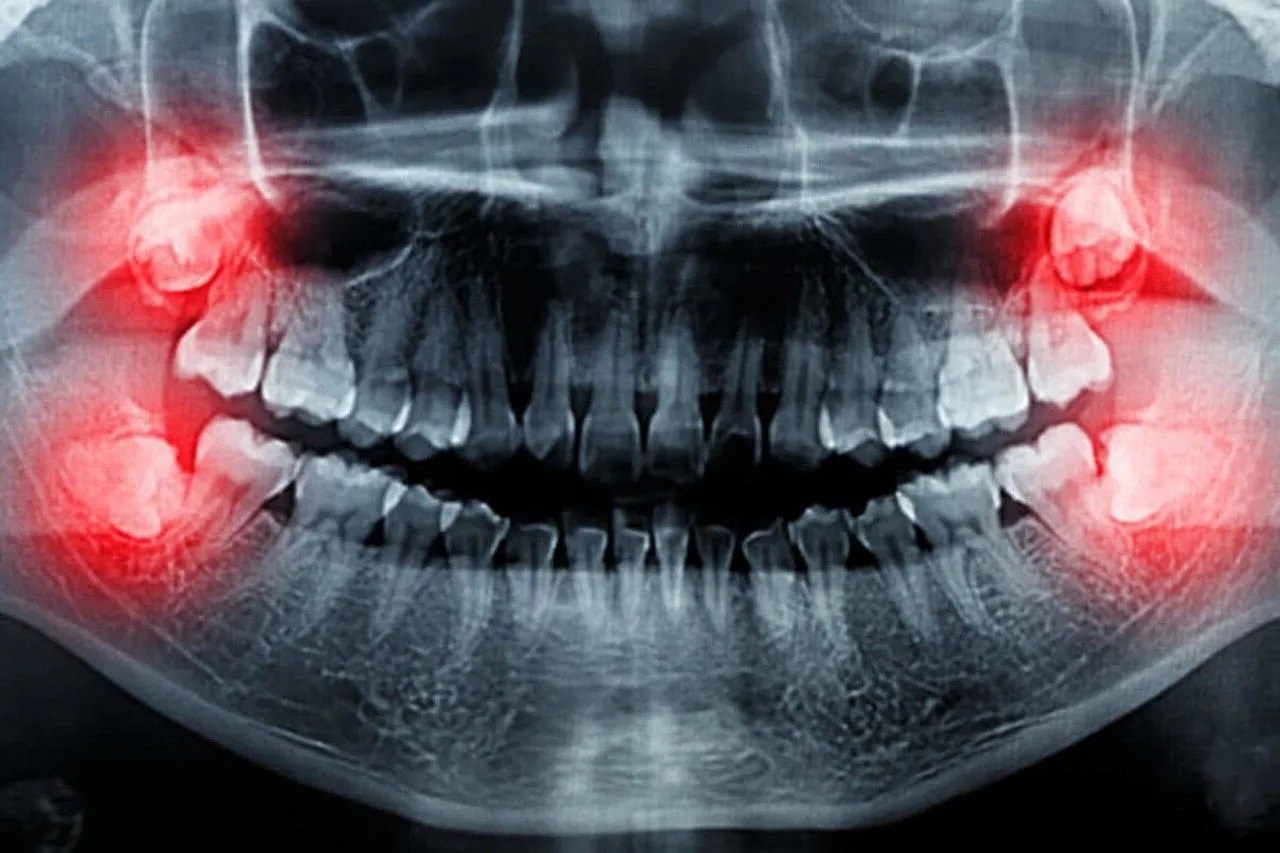

Yirmilik dişlerin sorun yaratmasının temel nedeni, günümüz insanının çene yapısının bu dişlerin sürmesi için yeterli alanı sunmamasıdır. Geçen asırlar içerisinde insan çenesi küçülürken, yirmilik dişler aynı boyutta kalmıştır. Bu durum, yirmilik dişlerin ya tamamen gömülü kalmasına (çene kemiği veya diş eti altında) ya da yarı gömülü sürmesine neden olur. Yetersiz sürme alanı, dişin doğru pozisyonda çıkmasını engeller ve çeşitli sorunlara yol açar:

- İltihap ve Enfeksiyon (Perikoronitis): Yarı gömülü süren yirmilik dişlerin üzeri genellikle bir miktar diş eti ile kaplı kalır. Bu bölge, bakteri ve yiyecek artıklarının birikmesi için ideal bir ortam oluşturur. Bu durum, şiddetli ağrı, şişlik, kızarıklık ve hatta ağız kokusuna neden olan iltihaplanma (perikoronitis) riskini artırır.

Yirmilik dişlerin neden olduğu problemler genellikle cerrahi müdahale ile çözülür. Diş hekimleri, röntgen ve detaylı muayeneler sonucunda yirmilik dişin konumunu, gömülü olup olmadığını ve çevre dokulara etkisini değerlendirerek çekim kararı alabilirler. Bazen, henüz sorun yaratmamış olsa bile, gelecekte problem yaratma potansiyeli yüksek olan yirmilik dişlerin önleyici olarak çekilmesi de önerilebilir. Bu tür müdahaleler, ağız ve çene cerrahları tarafından steril koşullarda gerçekleştirilir.